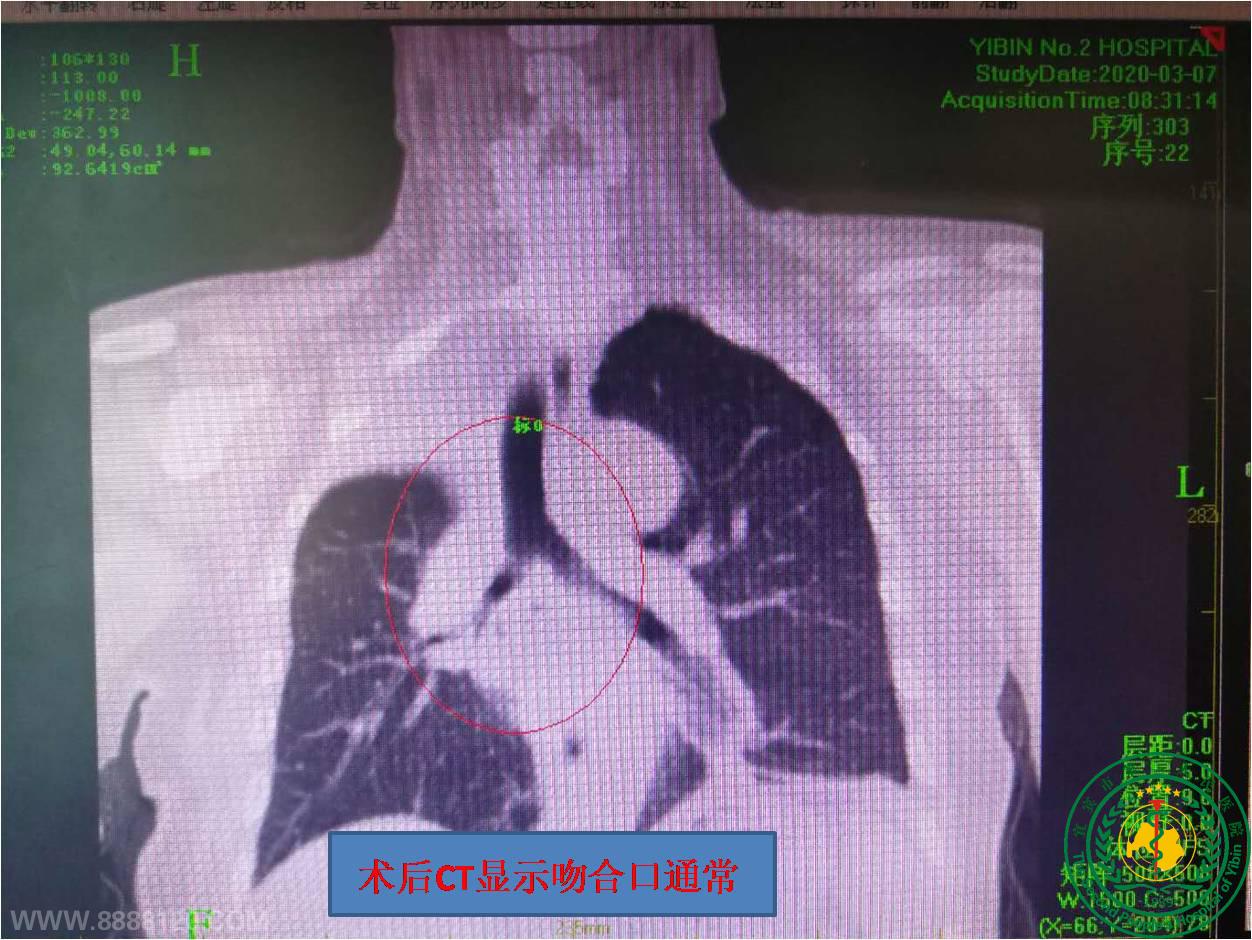

我院率先在川中南独立成功开展胸腔镜袖式肺叶切除半隆突成形术

我院率先在川中南独立成功开展胸腔镜袖式肺叶切除半隆突成形术25951